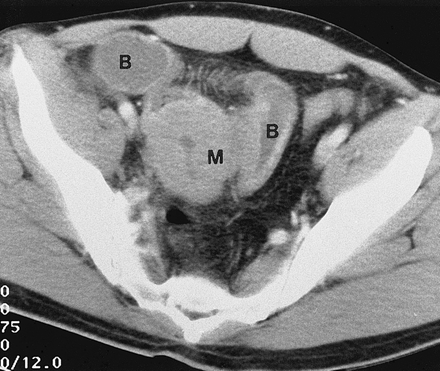

Chụp cắt lớp vi tính (CT Scan) hoặc các xét nghiệm khác với ruột non để thiết lập chẩn đoán.